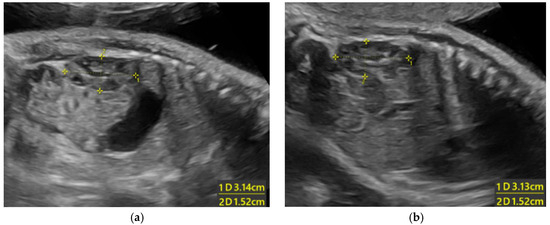

| Small kidneys | N.R. | N.R. | N.R. | N.R. | N.R. | N.R. | N.R. | N.R. | N.R. | N.R. | N.R. | N.R. | N.R. | + |

| Large BPD | N.R. | N.R. | N.R. | N.R. | N.R. | N.R. | N.R. | NR | N.R. | N.R. | N.R. | N.R. | + | - |